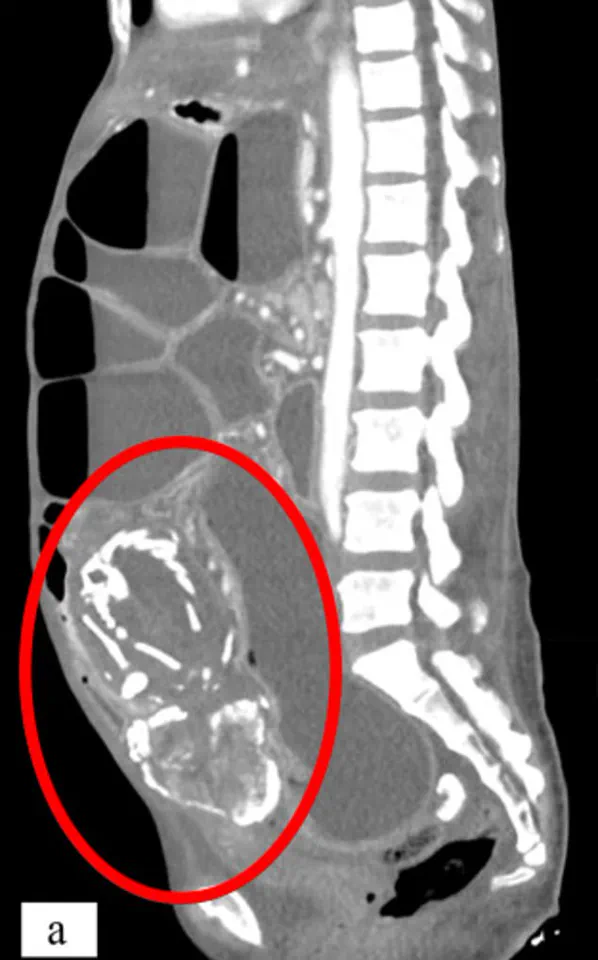

Medical experts emphasize that the body's response to a nonviable pregnancy is both complex and protective. When the fetus dies, the immune system recognizes it as a foreign object, triggering a process that encases the remains in calcium to prevent infection. This mummification can lead to a mass that causes chronic pain, digestive issues, or even life-threatening complications if left untreated. In 2023, a 50-year-old woman in New York experienced severe malnutrition after a lithopedion compressed her intestines for nine years. Her condition went undiagnosed until scans revealed the calcified fetus, which she had mistakenly attributed to a spiritual curse.

Another tragic example involves an 81-year-old woman in Brazil who died after surgery to remove a lithopedion she had carried for over 56 years. Doctors discovered the calcified mass during a routine scan for stomach pain, revealing a fetus from a pregnancy more than half a century prior. These cases underscore the importance of early detection through modern prenatal imaging and blood tests. Today, healthcare professionals use detailed ultrasounds and hormone monitoring to identify pregnancies of unknown location (PUL), ensuring timely treatment with medication or surgery.